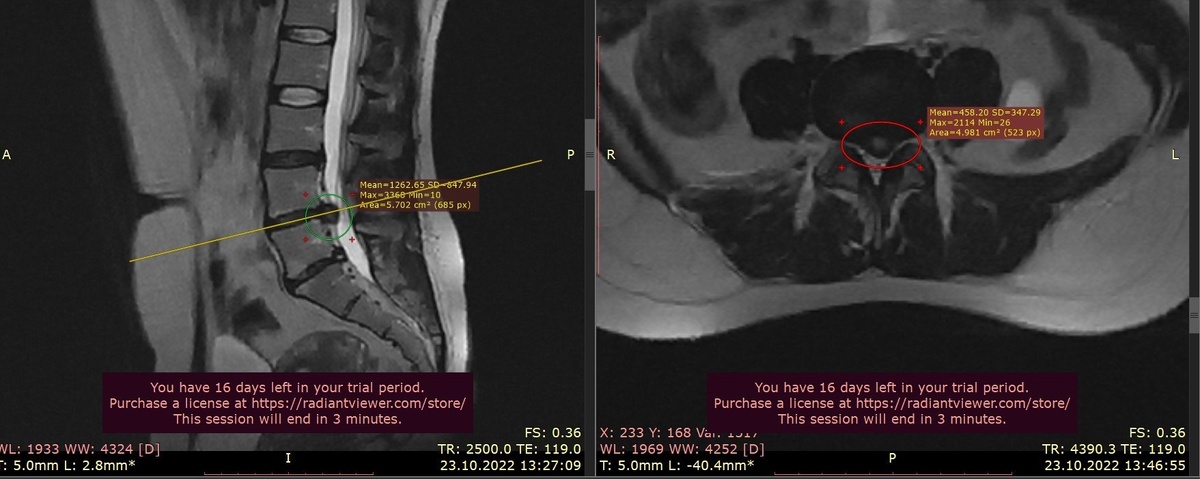

Если бы Анна обратилась сразу, когда боль только появилась ( третий снимок мрт),

процесс мог занять значительно меньше времени.